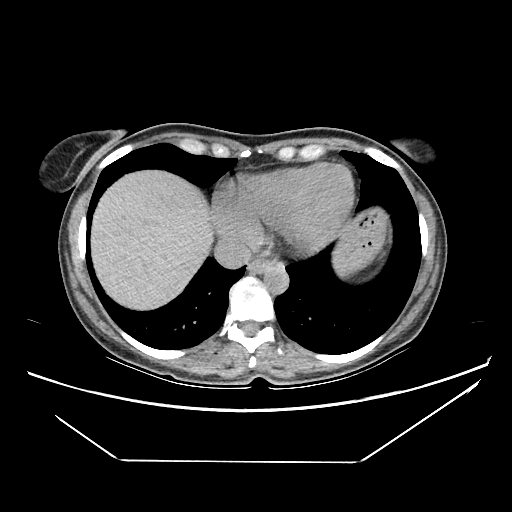

Original NATIVE CT scan (input)

Full window (WL 1023.5, WW 4095 β†’ Low βˆ’1024, High +3071)

Actual HU range: [-160.0, 240.0]